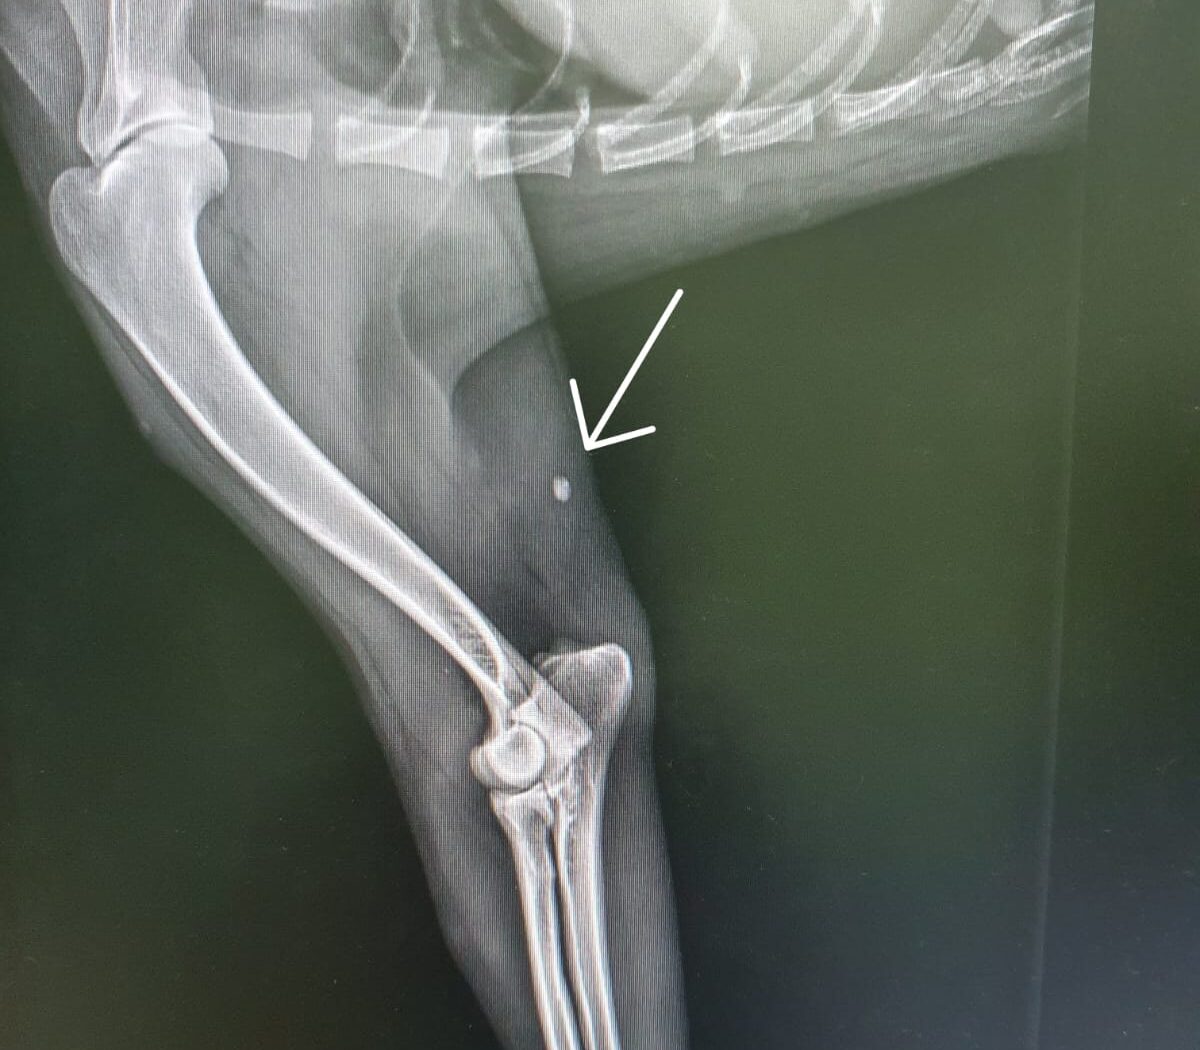

Blanca allerdings wurde total abgemagert und schwach aufgelesen. Da sie nicht einmal gehen konnte, wurde ein Röntgen gemacht um zu schauen, ob etwas gebrochen war. – Sie war aber einfach nur total unterernährt.

Das Röntgenbild zeigte jedoch eine Schrotkugel im Bein, die Blanca aber in keiner Weise stört.(s.Photo)